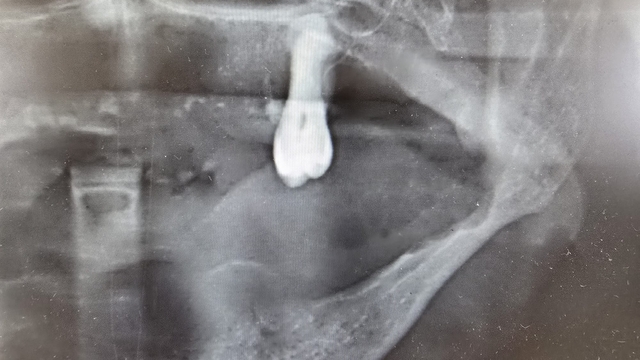

Ağız kanserinde erken tanı gerçekleşirse hastaların ölümle sonuçlanmasının önüne geçilebileceğini ifade eden Prof. Dr. Gündüz, “Biz kurum olarak Karadeniz'in en büyük üniversitesiyiz ve de fakülte olarak da Karadeniz'de büyük bir hizmet vermekteyiz. Ortalama yaklaşık günde 500 hasta, aylıkta 10 bine yakın hasta bakıyoruz. Biz yapmış olduğumuz seminerlerde hem öğrencilerimizi hem asistanlarımızı hem de halkımızı bu konuda bilgilendirmeye çalışıyoruz. Erken tanı eğer gerçekleşirse bu hastalıkların ölümle sonuçlanmasının nispeten önüne geçmiş oluyoruz. Çünkü erken tanı biliyorsunuz her kanser vakasında çok önemli bir yer tutmakta. Herhangi birisi ağzında eğer 2 haftanın üzerine geçmeyen bir yara varsa mutlaka en yakın diş hekimine başvurması gerekmekte. Sebepsiz yere dişlerin sallanması, uyuşukluk olması, yüzde sebepsiz ağrıların, çene bölgesinde sebepsiz ağrıların oluşması kanserlerin başlangıç bulguları arasındadır. Zaten kanserlerin en fazla oluştuğu yerler ağız içerisinde dilin özellikle arka kenarlarıdır. Bunlar ne yazık ki başlangıçları da ağrısız olduğu için bir kısmının gözden kaçabilmekte. O yüzden insanlarımızdan, halkımızdan bu konuda dikkat etmeleri, eğer böyle bir lezyonla muhatap olurlarsa mesela bir yakınından ağız içerisindeki görüntüsünü çekmesini talep etmeli. 2 hafta sonra da aynı şekilde bu görüntü duruyorsa veya daha da büyümüşse en yakın merkeze gitmesini önermekteyiz” ifadelerini kullandı.